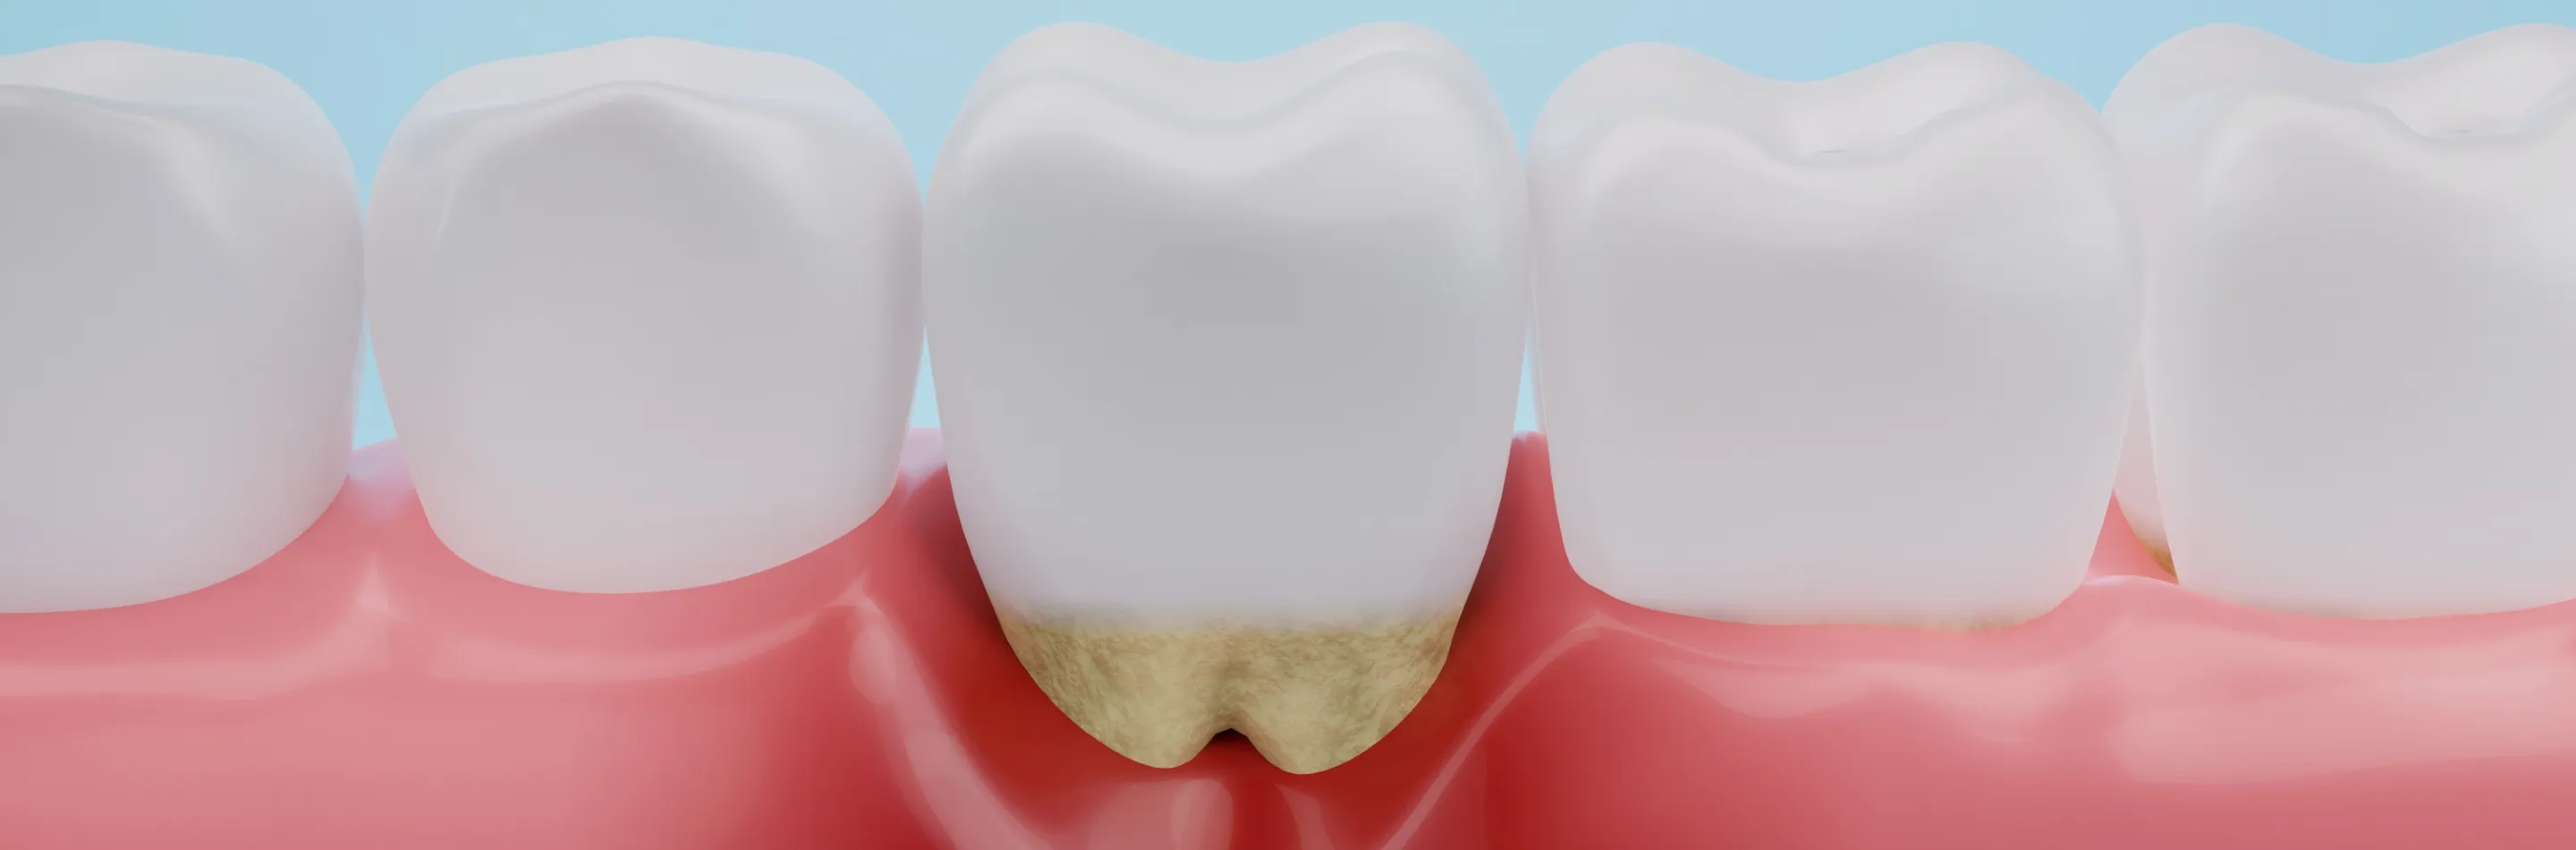

歯周病の原因となる細菌に感染し、歯肉や歯を支える歯槽骨といった組織が炎症を起こして溶けていく病気です。細菌が集合している歯垢という汚れが歯と歯周ポケット(歯肉の溝)に溜まり、これを除去できずにいると石灰化して歯石になります。歯石はブラッシングでは取り除くことができず、炎症を拡大させていきます。

歯周病の進行

- STEP 01

歯肉炎

歯肉だけに炎症が起きており、骨にはまだ影響がありません。歯肉が赤く腫れるほか、歯磨きのときに出血することがあります。丁寧な歯磨きで改善できます。

- STEP 02

軽度歯周炎

歯肉がさらに赤く腫れるとともに、歯周ポケットが深くなります。歯垢や歯石が溜まるようになり、骨が溶け始めて歯肉が下がってきます。